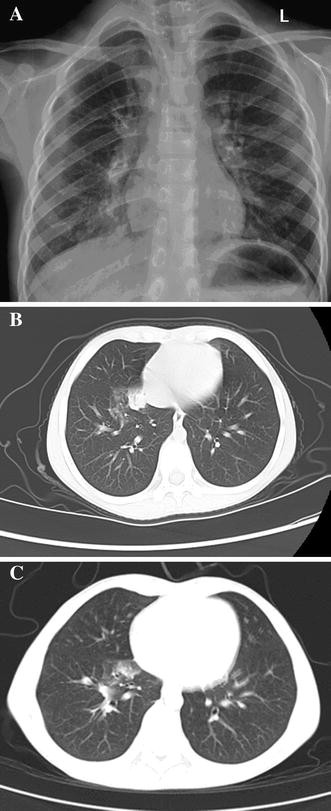

The index case was a 7-year-old girl who was from a family of chicken dealers. She presented with fever, cough and discomfort on 11 April 2013 at 9:00 a.m. She was admitted to Beijing Ditan Hospital, Captial Medical University with a temperature of 38.6 °C. After admission, she underwent radiological and blood tests. Chest radiography showed patchy opacities and edge effusion on bilateral lungs (Fig. 1a).

a Chest radiographs of the index case showing patchy opacities and edge effusion on bilateral lungs 5 h after fever. b, c chest computed tomography (CT) scan of the index case: b consolidation in the right lower lobe 15 h after onset of fever, c improvement 3 days after treatment with oseltamivir. The lung shadow of consolidation had became absorbed

After admission, this patient developed fever (maximum temperature 40.2 °C) which could not be brought under control with the administration of acetaminophen (2 ml orally). By 15 h after the fever began, her respiratory rate had risen to 35 breaths per minute and finger oxygen saturation had dropped to 95–96 %. The breath sounds of her right lung became weak, and fine moist rales could be heard, with the intensity of the right lung’s breath sound decreasing. Chest CT scan showed right lower lobe consolidation (Fig. 1b). The pharyngeal swab was positive for influenza A using a rapid influenza diagnostic test based on the presence of influenza A antigens. Subsequently, oseltamivir (45 mg twice daily) was prescribed to the patient. The specimens sent to the Beijing Center for Disease Control and Prevention (CDC) and the Chinese National Influenza Center (CNIC) tested positive for H7N9 virus. The patient’s temperature dropped to 36.2 °C 18 h after the initiation of treatment with oseltamivir. Cough and other symptoms alleviated rapidly. The chest CT scan showed improvement 3 days after disease onset (Fig. 1c).